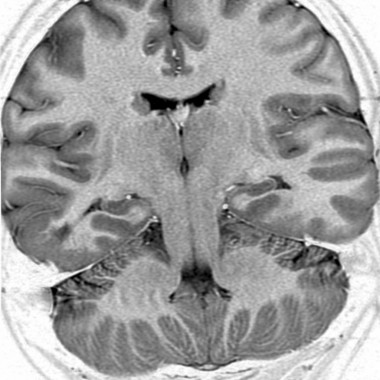

Dysplasie corticale focale temporale droite

Case courtesy of Dr Frank Gaillard, Radiopaedia.org. From the case Focal cortical dysplasia – type I